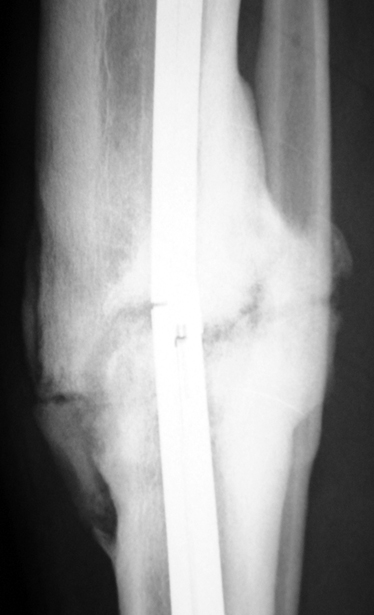

Recently, ilizarov techniques which is basis depend on distraction osteogenesis , bone segment transport or acute shortening after the resection at the site of pseudarthrosis combined with lengthening at another level of bone have been used. These treatment techniques may include some advantage for problems of infection, leg-length discrepancy, soft-tissue loss, and joint contracture.

Management of Stiff Hypertrophic Nonunions by Distraction Osteogenesis – A Report of 16 Cases

Tibial nonunion